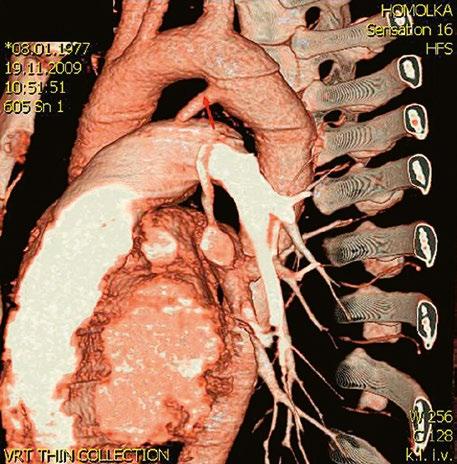

Supravalvární pulmonální stenóza a stenózy větví plicnice bývají součástí komplexních VSV (např. Fallotovy tetralogie) nebo syndromů (Williamsův syndrom, syndrom Noonanové, syndrom vrozené rubeoly, Alagillův syndrom aj.) (Obr. 45.39). Získané stenózy větví plicnice, ale i úplný uzávěr větve plicnice můžeme vidět po spojkových operacích podle BlalockaTaussigové (Obr. 45.40, Obr. 45.41). Pro zobrazení supravalvárních a periferních stenóz plicnice je optimální CT angiografie (Obr. 45.40, Obr. 45.41, Obr. 45.42, Obr. 45.43).

Obr. 45.40 CT angiografie, 8mm stenóza a deformace levé větve plicnice (šipka) po spojkové operaci podle BlalockaTaussigové v dětství LPA – levá větev plicnice, PA – kmen plicnice, RPA – pravá větev plicnice

Obr. 45.41 Uzávěr levé větve plicnice jako následek provedené spojky podle BlalockaTaussigové v dětství, CT angiografie